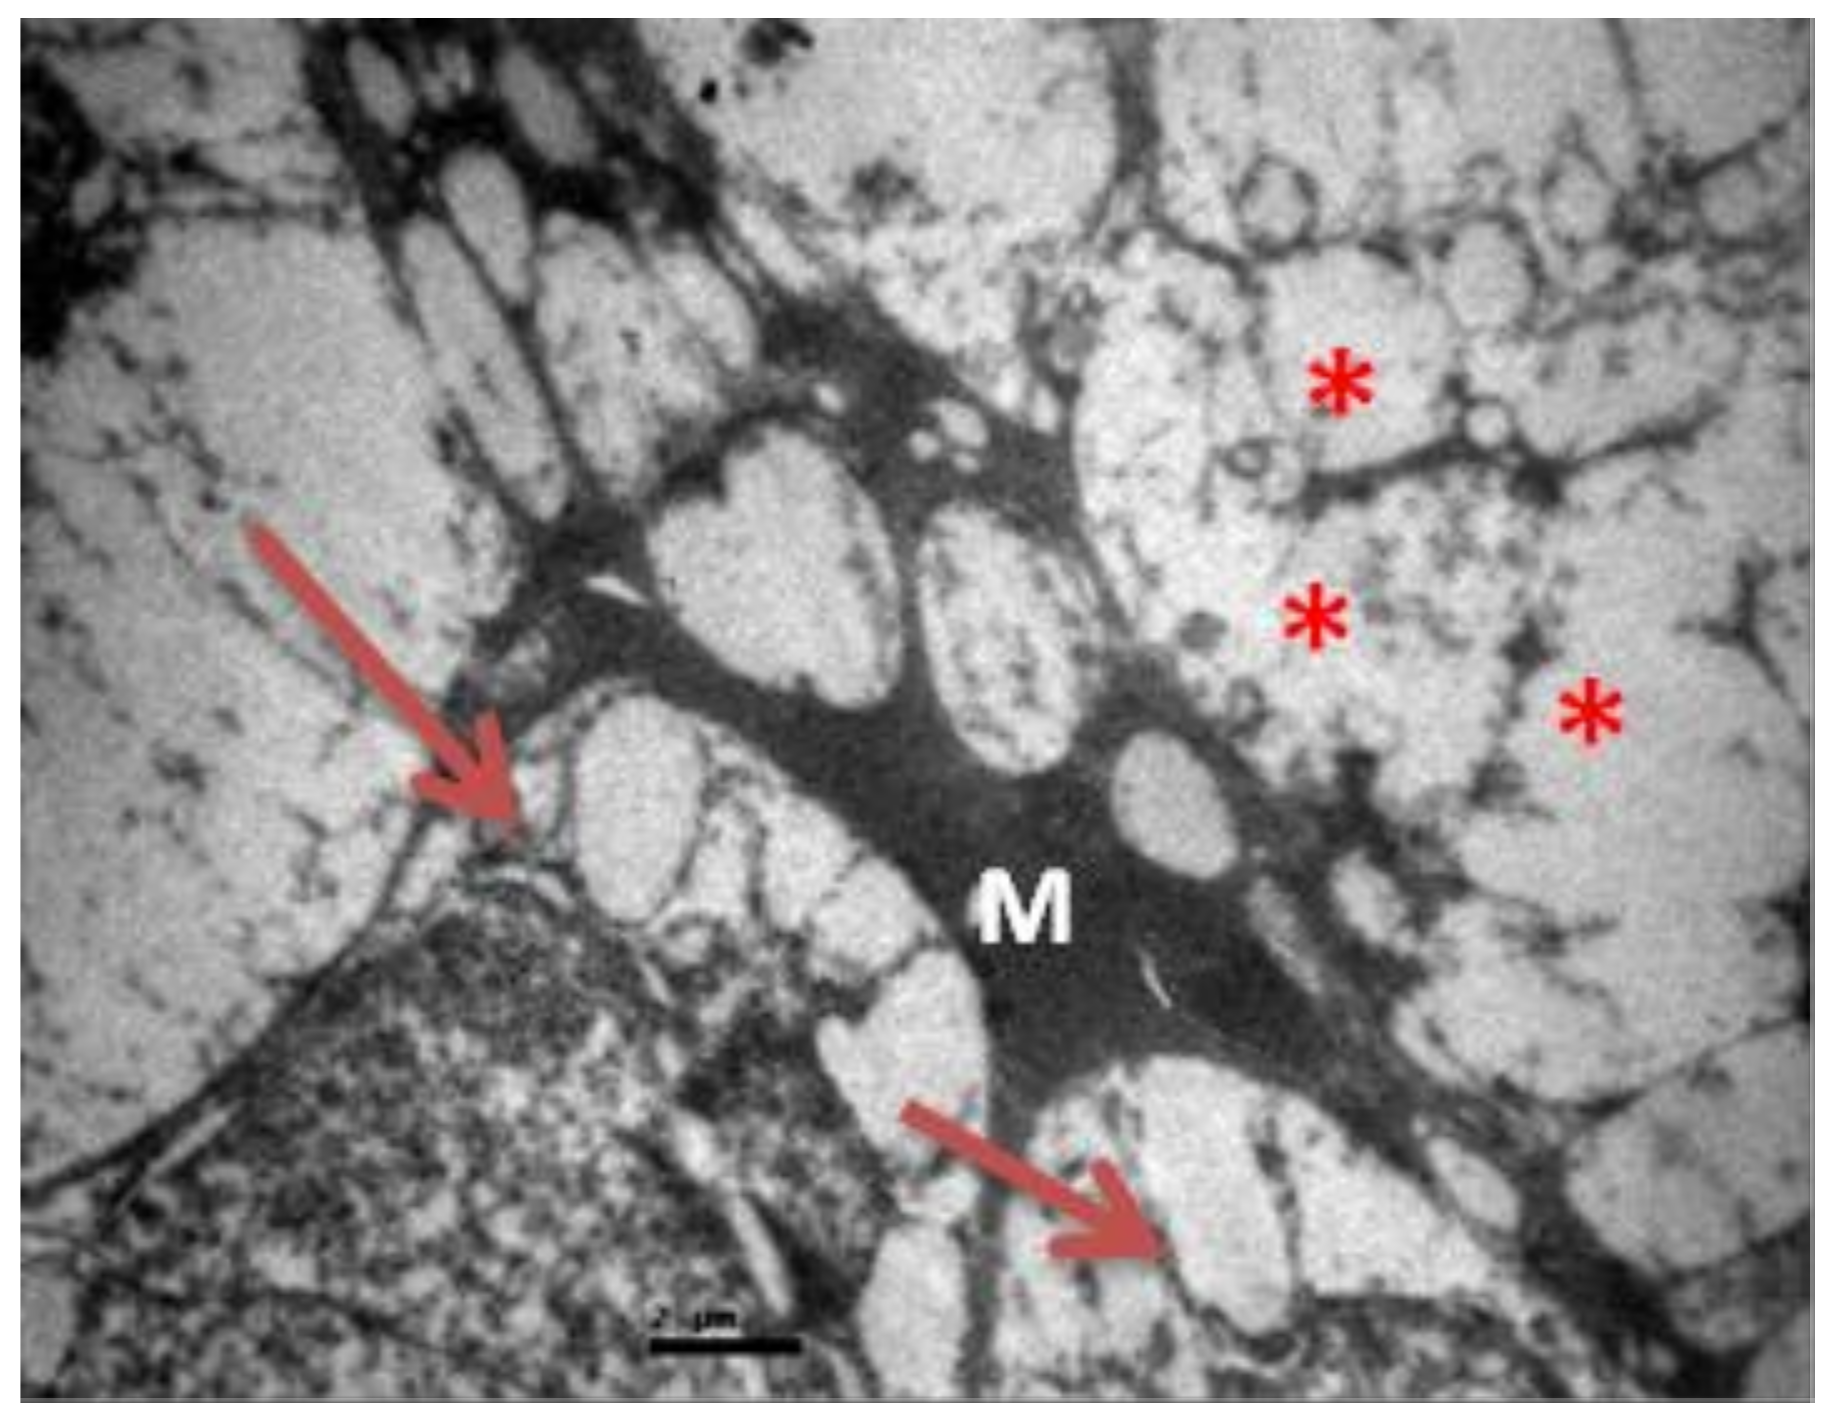

2.3. Group M